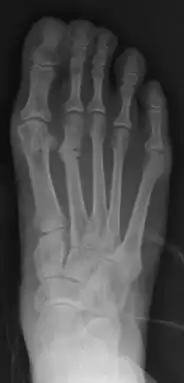

Stress fracture of the second metatarsal bone (below the knuckles of the second toe)